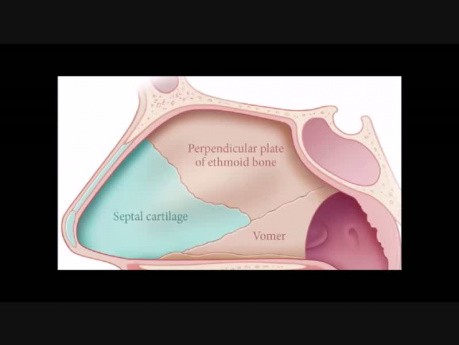

Septoplastyka

Film przedstawia technikę wykonania plastyki przegrody nosa. Materiał przygotował dr Steven Houser.